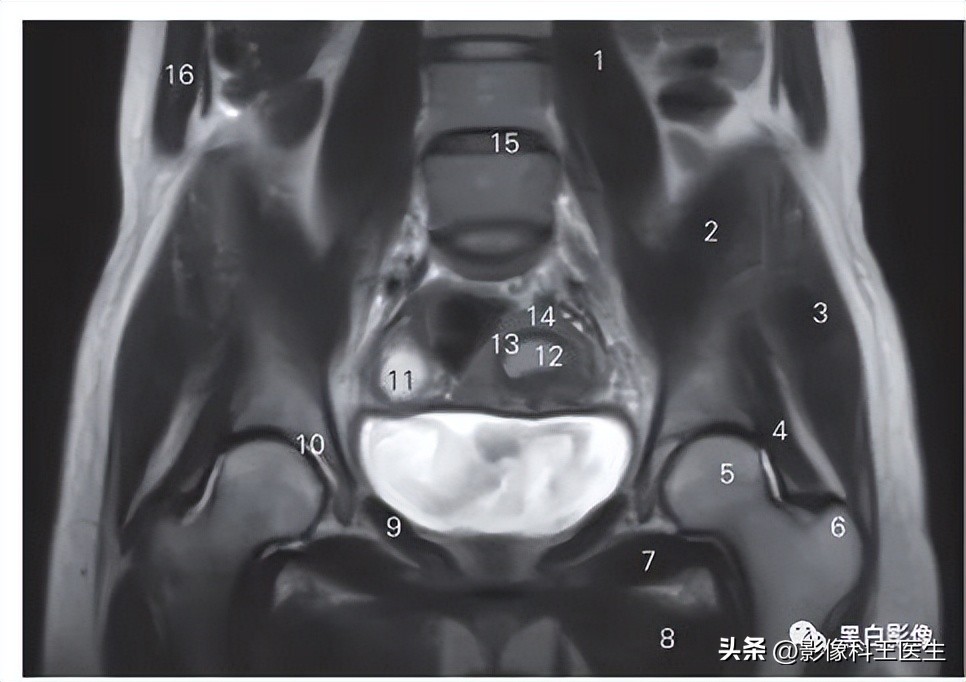

图8-3 经子宫腔、膀胱和股骨颈的冠状断层MR T2加权图像

1 腰大肌 psoas major 2 髂肌 iliacus

3 臀中肌 gluteus medius 4 臀小肌 gluteus minimus

5 股骨头 head of femur

6 股骨大转子 greater trochanter of femur 7 闭孔外肌 obturator externus

8 大收肌 adductor magnus 9 闭孔内肌 obturator internus

10 髋臼 acetabulum 11 卵泡 follicle

12 子宫内膜 endometrium of uterus 13 子宫结合带 uterine junction zone

14 子宫肌层 mesometrium of uterus

15 第4腰椎间盘 4th lumber intervertebral disc

16 腹外斜肌 obliquus externus abdominis

图8-4 经闭孔和膀胱的冠状断层MR T2加权图像

1 腰大肌 psoas major 2 臀中肌 gluteus medius

3 臀小肌 gluteus minimus 4 闭孔内肌 obturator internus

5 闭孔外肌 obturator externus 6 大收肌 adductor magnus

7 股骨干 femoral shaft

8 股骨大转子 greater trochanter of femur 9 髋臼 acetabulum

10 膀胱 urinary bladder 11 子宫 uterus

12 直肠 rectum

13 第1骶椎椎体 1st sacral vertebral body 14 髂骨翼 ala of ilium

15 脑脊液 cerebrospinal fluid